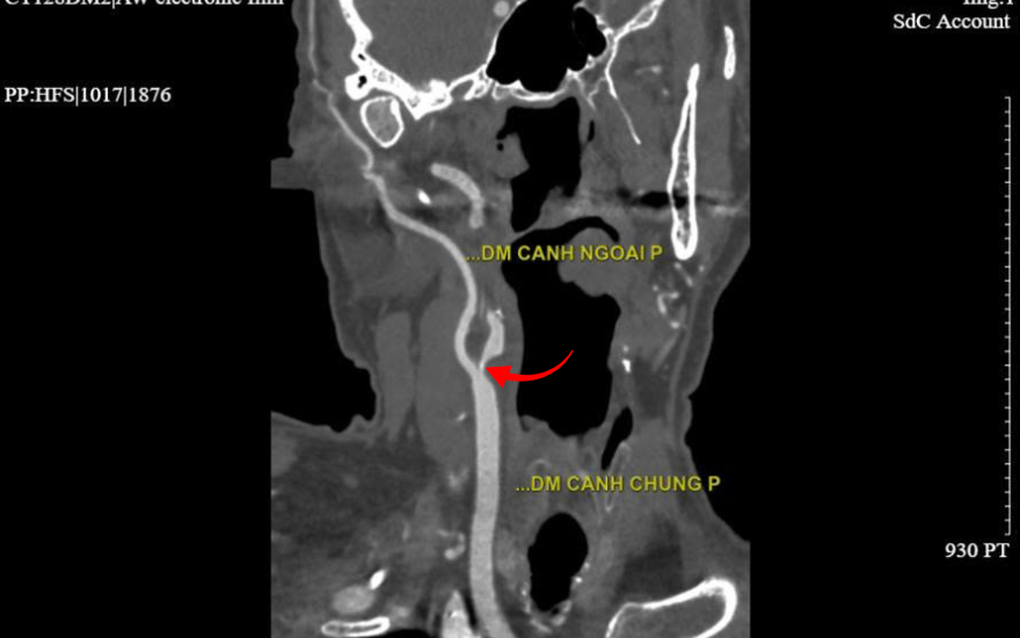

Các kết quả thăm dò cận lâm sàng sau đó cho thấy động mạch cảnh trong bên phải của người bệnh bị hẹp rất khít (trên 90%) ngay từ lỗ vào, kèm theo nhiều mảng xơ vữa. Ngoài ra, hệ mạch vành cũng ghi nhận hẹp trên 90% tại động mạch liên thất trước.

Vị trí hẹp mạch cảnh trên hình ảnh chụp CT 2560 lát cắt (Ảnh: BVCC).